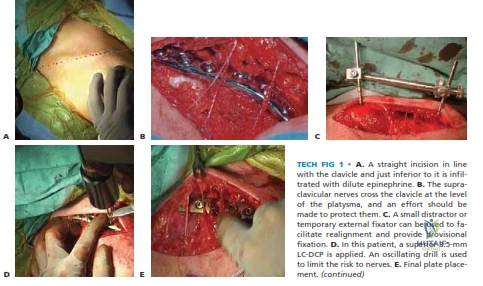

This topic focuses on Clavicle Tech Fig: Plate Fixation for Lasting Repair, Displaced, comminuted clavicle fractures, often resulting from direct blows, risk nonunion and malunion. These can be considered for open reduction and internal fixation using a plate and screws. The risk of nonunion for completely displaced and comminuted fractures is 10-20% (refer to clavicle tech fig 1), potentially causing shoulder deformity or brachial plexus compression.

The clavicle is subcutaneous throughout its length, contributing prominently to the aesthetic contour of the neck and upper chest. This superficial location, however, places overlying neurovascular structures at risk during surgical exposure. Critically, the supraclavicular nerves, originating from the cervical plexus (C3-C4), run obliquely across the clavicle just superior to the platysma muscle. These nerves provide sensation to the skin over the clavicle, upper chest, and shoulder. Meticulous identification and protection of these nerves during operative exposure are paramount to mitigate the risk of postoperative hyperesthesia, dysesthesia, or anesthesia over the chest wall. Deeper to the clavicle, the subclavian artery and vein, and the cords of the brachial plexus, lie in close proximity to the posterior and inferior aspects of the clavicle, particularly medially. This necessitates careful attention to screw length and trajectory during plate fixation to prevent iatrogenic neurovascular injury.

Careful incision through the skin and subcutaneous tissues is performed. The platysma muscle lies immediately deep to the subcutaneous fat. This muscle should be incised sharply in line with the skin incision. It is paramount to identify and protect the supraclavicular nerves, which originate from the cervical plexus (C3-C4) and typically cross the clavicle obliquely from superomedial to inferolateral. These nerves are usually located just superior to the platysma. Minimal dissection inferiorly along the clavicle and cautious retraction should be employed to reduce the risk of traction neuropraxia or direct injury to these sensory nerves, which can lead to bothersome dysesthesia or hyperesthesia in the distribution over the chest wall.